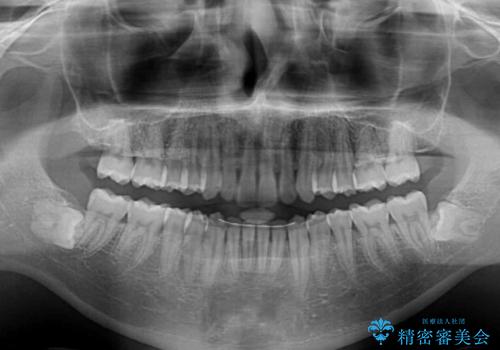

- 上下前歯のデコボコを気にして来院された患者様です。

全体的に叢生は軽度であったため、インビザラインにて矯正治療を行うこととしました。

デコボコの改善はもちろん、下顎前歯が隠れてしまうディープバイトも一緒に改善することができ、奥歯への負担を軽減することができました。